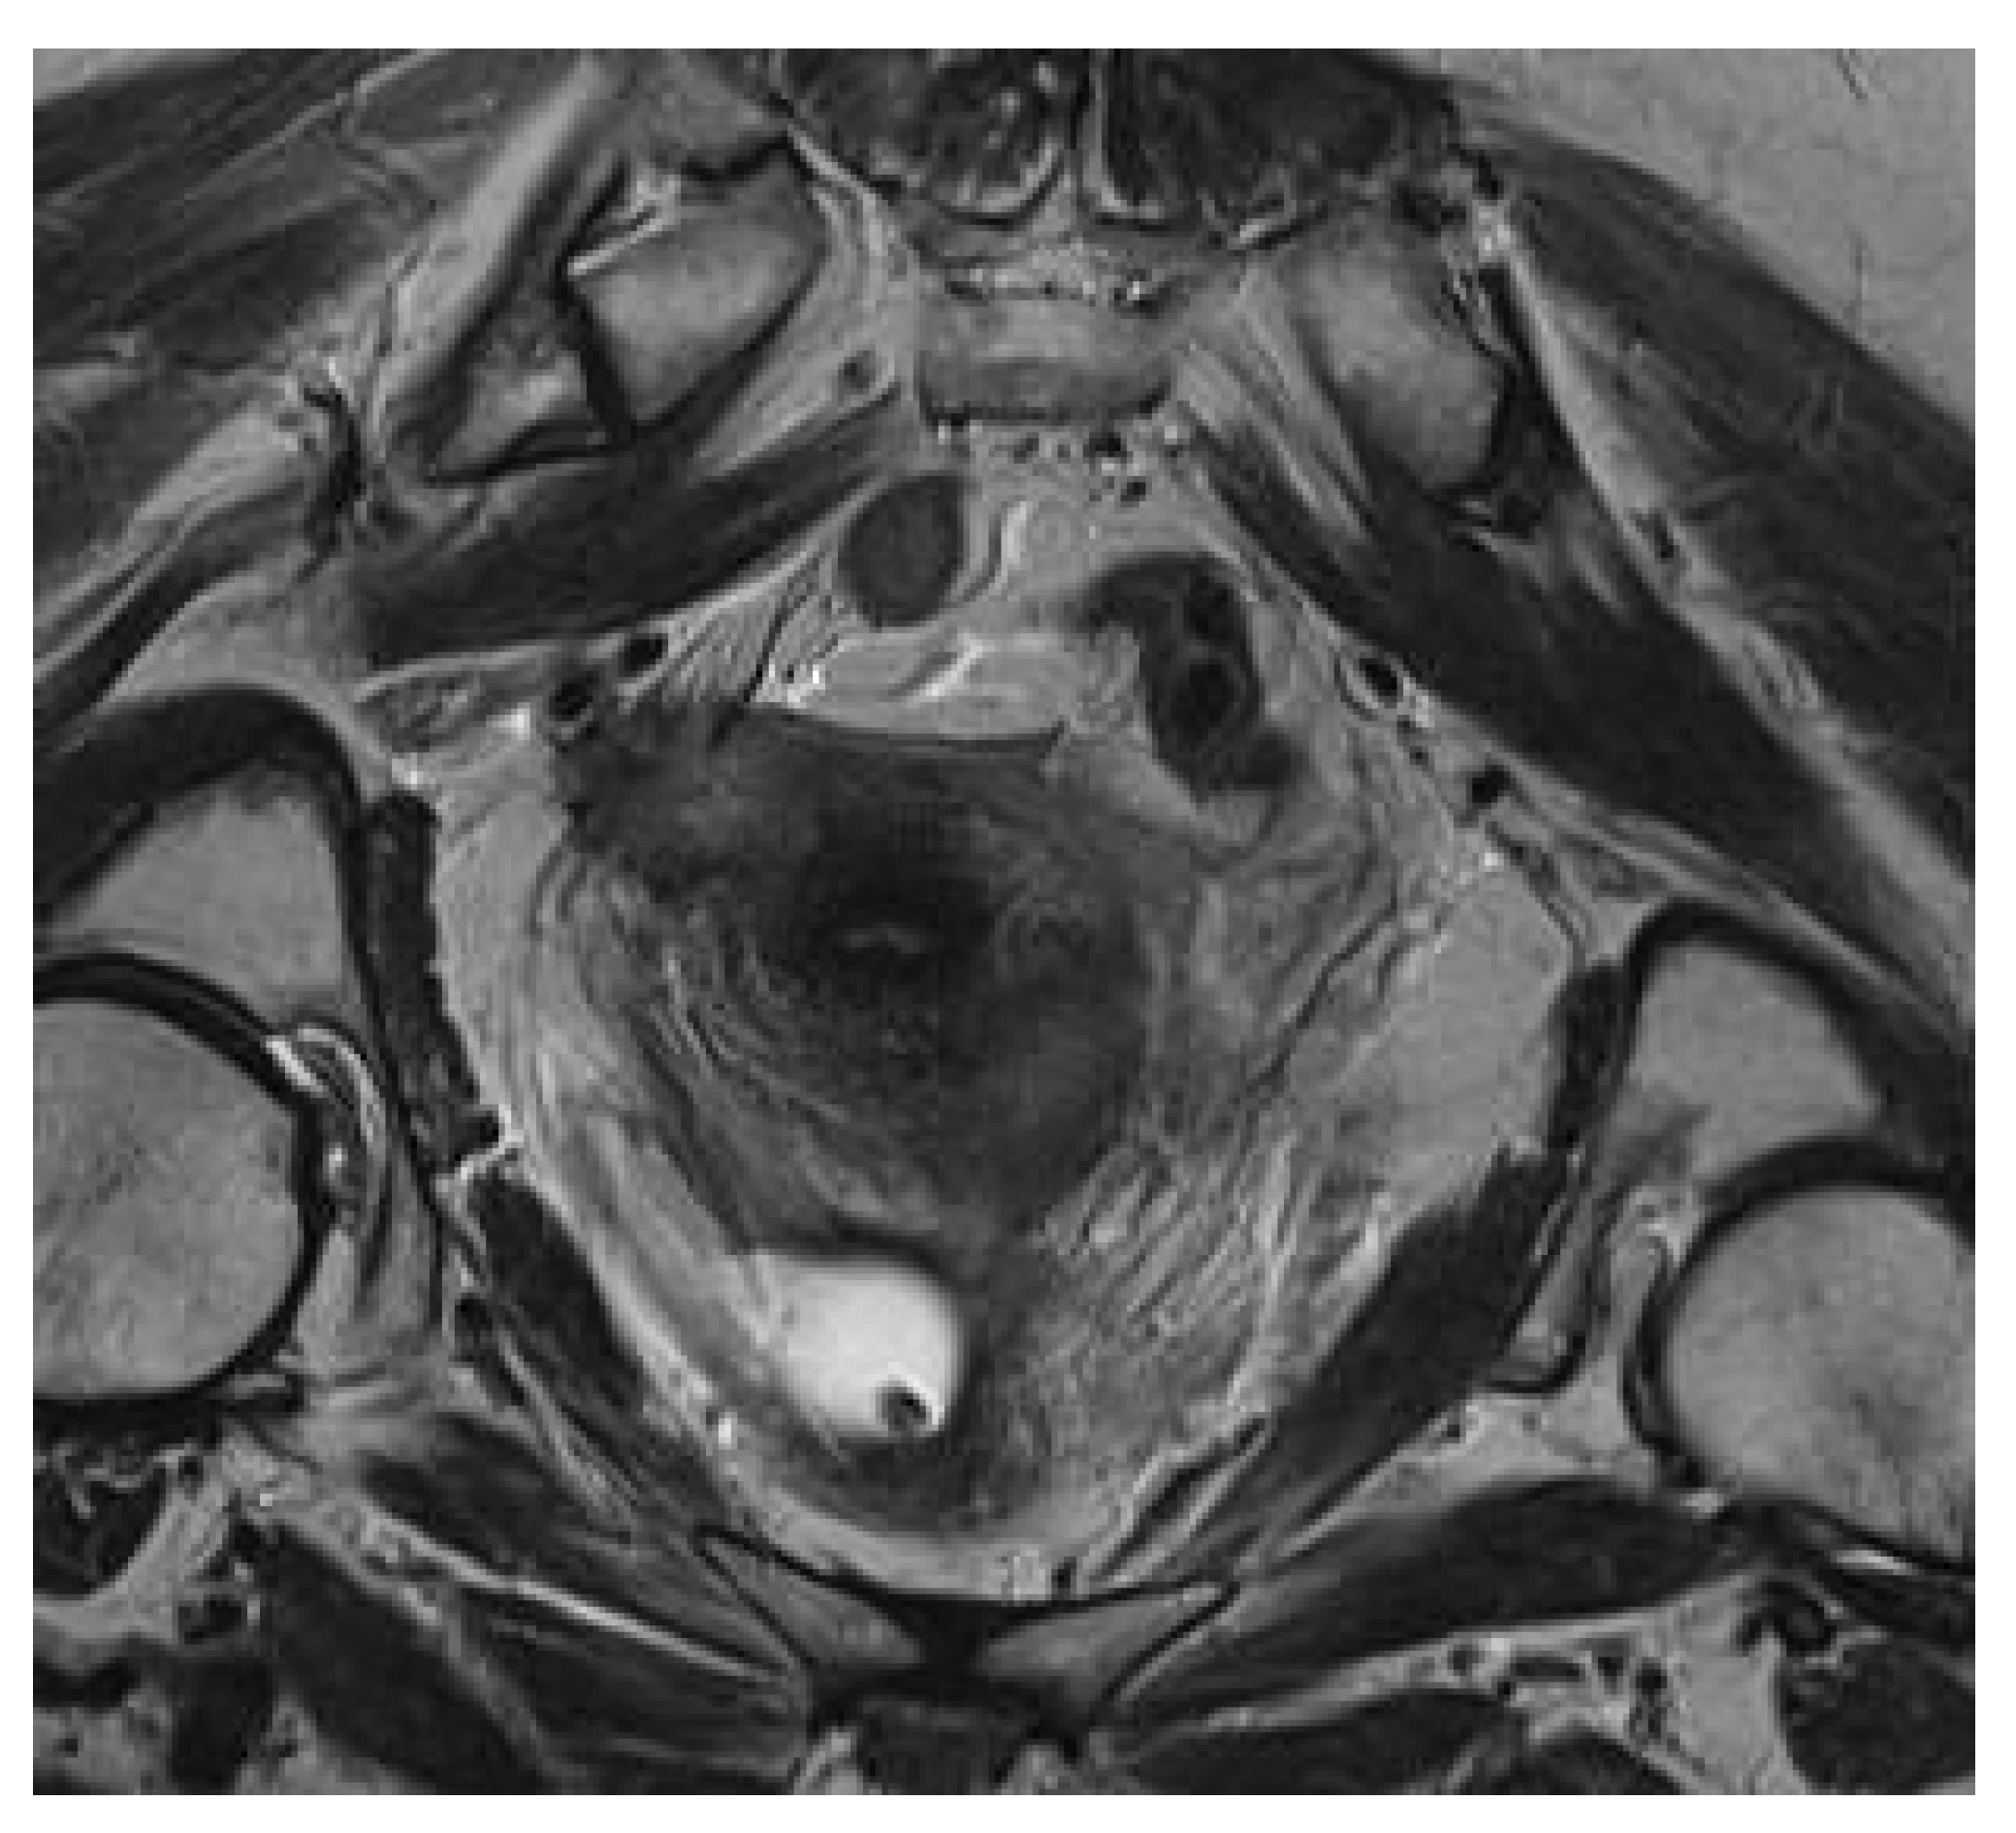

Krukenberg Tumor in Association with Ureteral Stenosis Due to Peritoneal Carcinomatosis from Pulmonary Adenocarcinoma: A Case Report

2. Case Report